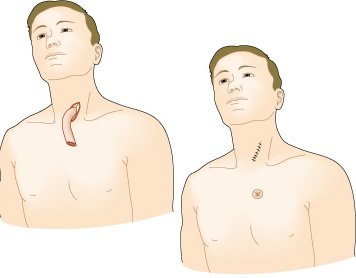

Mapa de linfonodos para câncer esofágico. A, Visão anterior. B, Visão lateral esquerda. C, Visão lateral direita. Estações ganglionares: l, supraclavicular; 2R, paratraqueal direito; 2L, paratraqueal esquerdo; 3P, mediastinal posterior; 4R, ângulo traqueobrônquico direito; 4L, traqueobrônquico esquerdo; 5, aortopulmonar; 6, mediastinal anterior; 7, subcarinal; 8M, paraesofagiano médio; 8L, paraesofagiano inferior; 9, ligamento pulmonar inferior; 10, hilar; 15, diafragmático; 16, paracardial; 17, gástrico esquerdo; 18, hepático comum; 19, esplénico; 20, celíaco A falta de serosa do esôfago tende a favorecer a extensão local do tumor.

Exposição do esôfago torácico superior através de uma esternotomia parcial superior. Ë demonstrado o trajeto do nevo laríngeo recorrente esquerdo pelo arco aórtico, e daí para o sulco traqueoesofágico.

A, A incisão cervical esquerda habitual estendida até a porção anterior do tórax na linha média, bem como a curva alternativa da incisão torácica anterior de pele evitam a formação de fibrose cicatricial na porção inferior do pescoço.

B, A incisão da esternotomia se estende da fúrcula supra-esternal através do manúbrio e atravessa o ângulo de Louis.